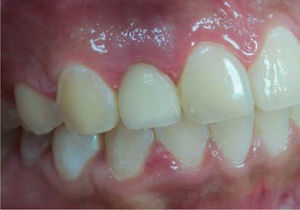

Reporte de Caso ClínicoMujer de 24 años con buen estado de salud general, consulta por inflamación marginal a nivel del incisivo lateral superior derecho con una profundidad al sondaje de 8 mm en vestibular y la presencia de una corona cerámica como restauración, sin antecedentes de hábitos parafuncionales (Figura 1).